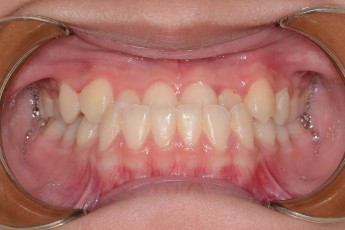

Before

After